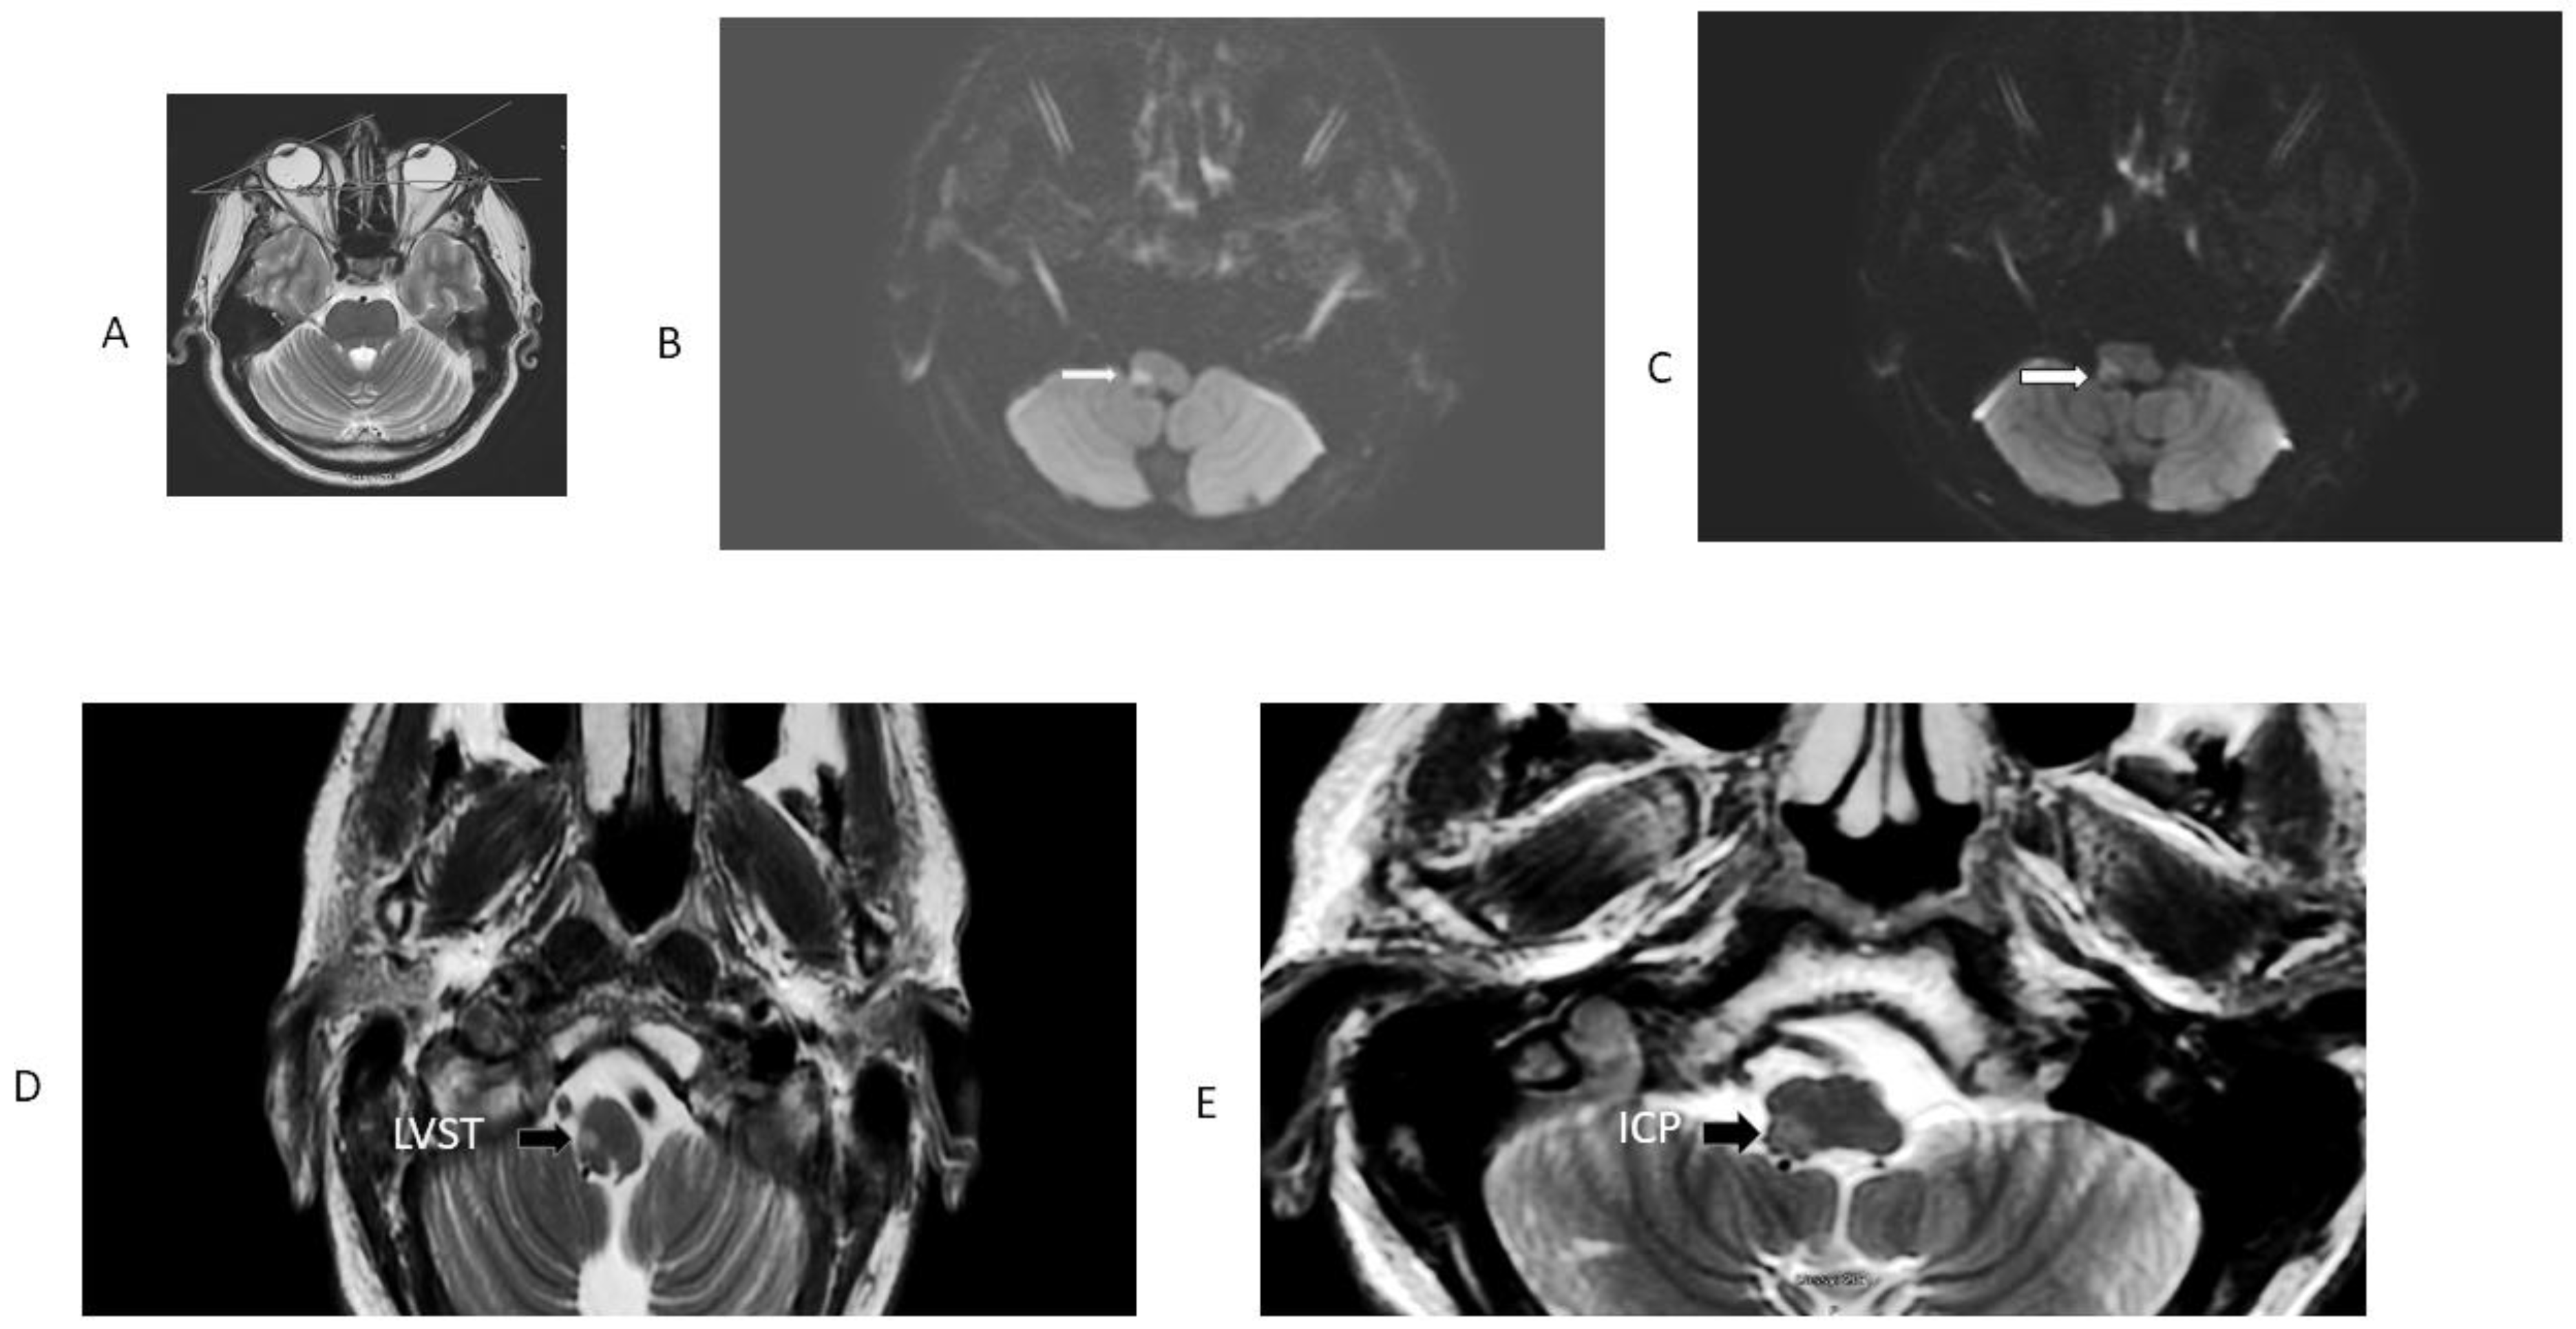

Figure 2.

MRI patient 9, Table 1. This patient had an initially false-negative MRI, the Figure shows the repeat MRI 48 h after initiation of symptoms. Note radiographic conjugate horizontal deviation of the eyes toward the right, in the same direction of OLD in a T2 axial MRI (panel (A)). Panel (B) is an axial DWI; it shows restricted diffusion involving the right LVST and the CSCT, responsible for severe right-side truncal and limb ataxia. The adjacent panel (C) is a 3 mm rostral axial DWI section at the level of the right inferior cerebellar peduncle, which explains OLD. The ADC map confirmed diffusion restriction. Panels (D) and (E) are T2 FLAIR images showing the same structures with greater anatomic resolution.